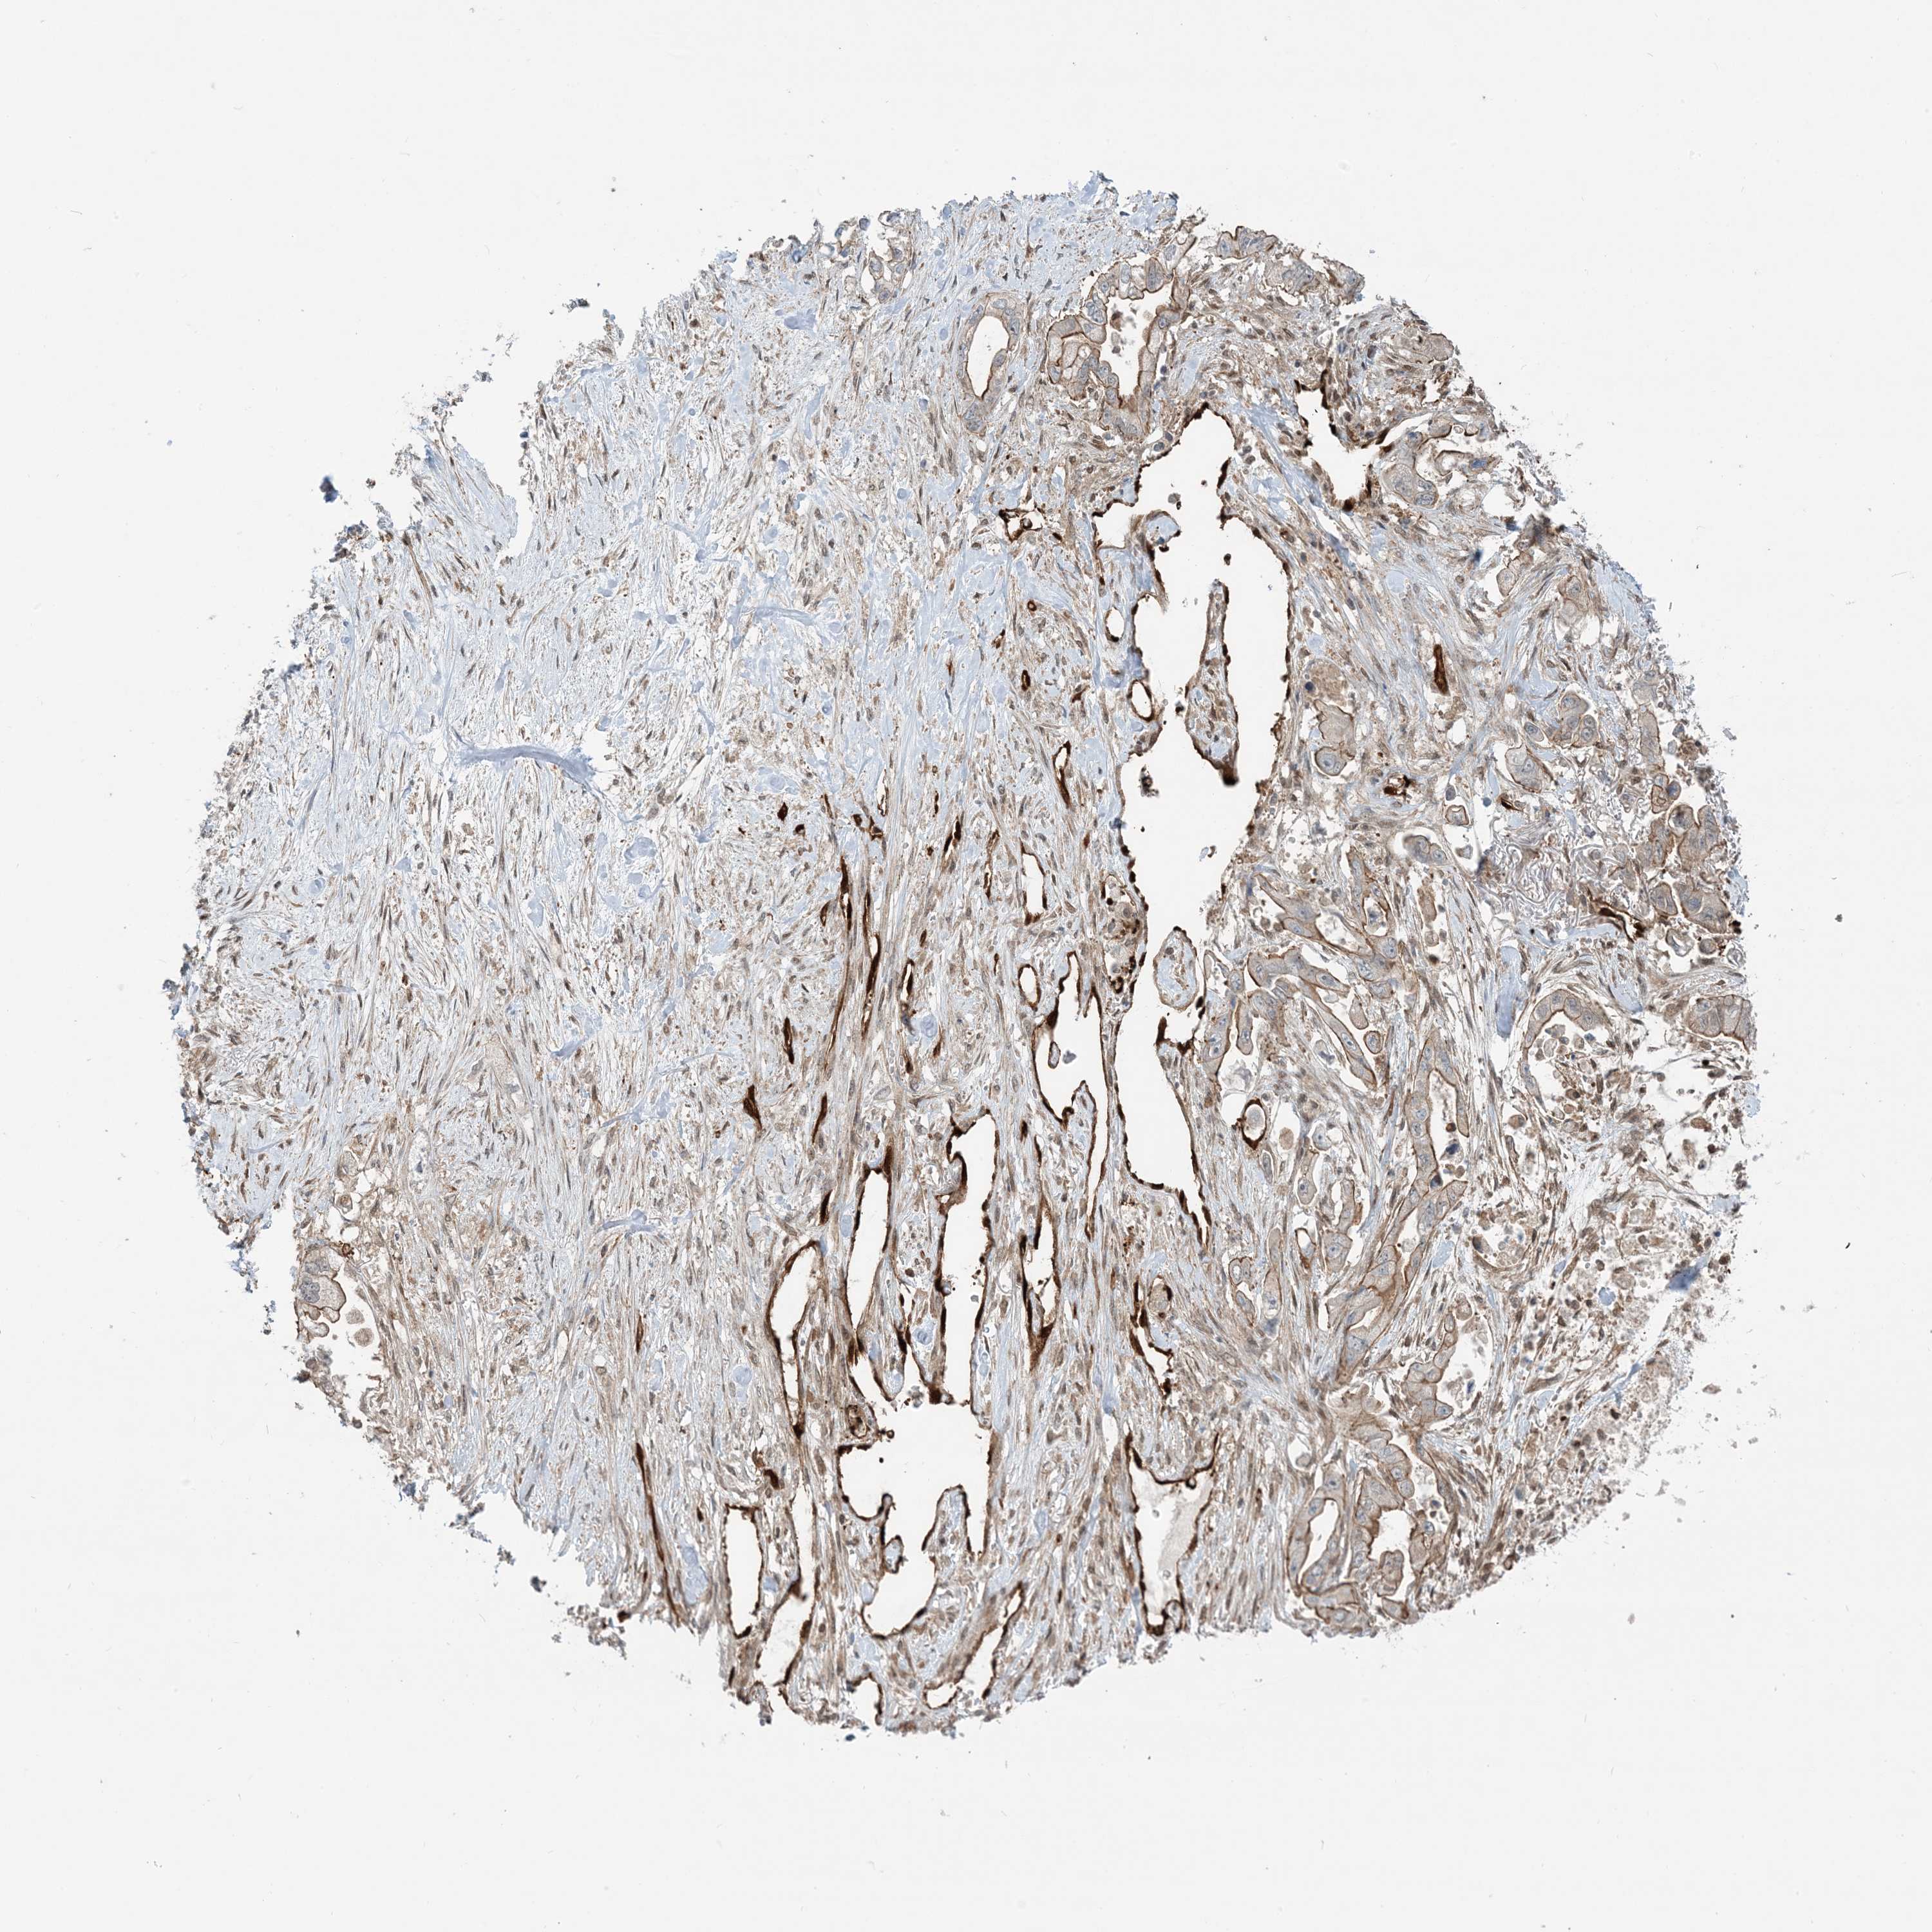

STOMACH CANCER - Protein expressioni

A mouse-over function shows sample information and annotation data. Click on an image to view it in a full screen mode. Samples can be filtered based on level of antibody staining by selecting one or several of the following categories: high, medium, low and not detected. The assay and annotation is described here.

Note that samples used for immunohistochemistry by the Human Protein Atlas do not correspond to samples in the TCGA dataset.

Antibody stainingi

Antibody staining in the annotated cell types in the current human tissue is reported as not detected, low, medium, or high, based on conventional immunohistochemistry profiling in selected tissues. This score is based on the combination of the staining intensity and fraction of stained cells.

Each image is clickable and will lead to virtual microscopy that enables deeper exploration of all samples and also displays staining intensity scores, fraction scores and subcellular localization as well as patient and tissue information for each sample.

Antibody HPA030989

Antibody HPA030990

Staining

High

Medium

Low

Not detected

Intensity

Strong

Moderate

Weak

Negative

Quantity

>75%

75%-25%

<25%

None

Location

Nuclear

Cytoplasmic/membranous

Cytoplasmic/membranous,nuclear

Adenocarcinoma, NOS